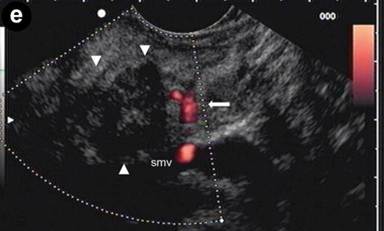

Patient#3: Focal form of autoimmune pancreatitis.

A 43-year-old man referred to us for abdominal pain and weight loss. IgG4 levels were elevated (298 mg/dL). Coronal scans with contrast enhanced CT (Image 3ab) showed the pancreatic head was enlarged with hypodense areas (2.7 cm, arrow) without vascular involvement of the mesenteric vessels. The pancreatic duct was dilated in both the body and the tail regions (arrowhead); the biliary tree was normal. The CT scan findings suggested pancreatic cancer. EUS and EUS-FNB were requested. Linear scanning (Image 3c) showed an enlarged pancreatic head with a focal hypoechoic mass (22 mm measured with calipers) with irregular margins (arrowheads). Upstream dilatation of the main pancreatic duct (8 mm, measured with calipers) in the body-tail regions was associated with the echopoor focal lesion (arrowheads); the lesion had close contact with the superior mesenteric vein (Image 3d). On EUS Doppler study (Image 3e), the echopoor lesion of the pancreatic head (arrowheads) appeared hypovascular; the superior mesenteric artery (arrow) and vein were patent.